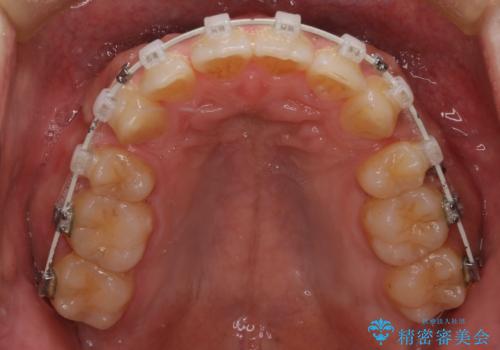

- 矯正装置

- 審美装置

最初はインビザラインを治療していた経緯がありますが、使用時間が確保できずワイヤー矯正へ移行しております。